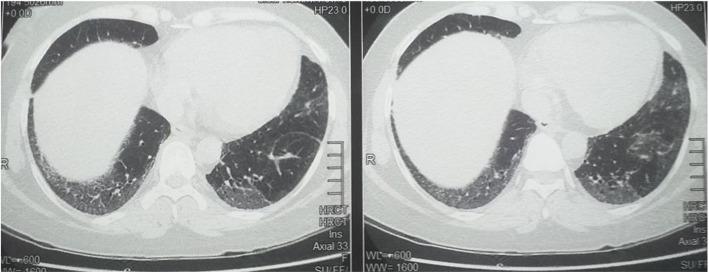

A 45-year-old female initially presented with a progressive proximal muscle weakness. Her muscle enzymes were elevated, EMG and biopsy were also in keeping with an inflammatory myositis. Subsequently she was found to have an interstitial lung disease with a non-specific interstitial pneumonitis pattern radiologically. Her anti Jo-1 was positive. However, she did not have any dermatological manifestations at the time. With immunosuppressive therapy she achieved remission which lasted for about 2 years. Then she developed fissuring and cracking of the palms and fingers suggestive of mechanic's hands without any muscle pain, weakness and elevation of muscle enzymes. A few months later she did develop muscle pain, weakness and elevation of muscle enzymes heralding a disease relapse.

一名45岁女性最初表现为进行性近端肌无力。她的肌酶升高,肌电图和活检也符合炎性肌炎。随后,她被发现患有间质性肺疾病,放射学表现为非特异性间质性肺炎模式。她的抗Jo-1抗体呈阳性。然而,当时她没有任何皮肤表现。经过免疫抑制治疗,她达到了缓解,持续了约2年。然后她出现了手掌和手指的皲裂和开裂,提示为技工手,没有任何肌肉疼痛、无力和肌酶升高。几个月后,她确实出现了肌肉疼痛、无力和肌酶升高,预示着疾病复发。